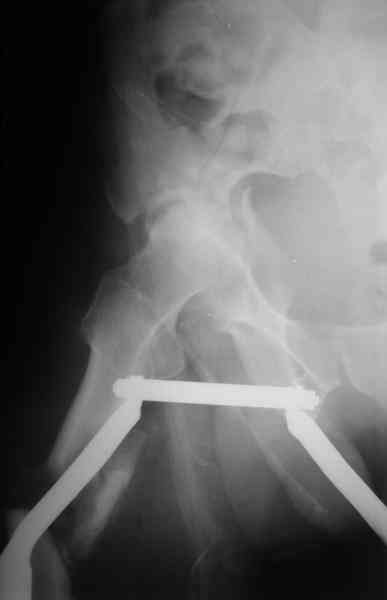

Уважаемы коллеги! Поступил непростой больной 24 лет через 1 месяц после травмы (фото в приложении). Кроме перелома правой вертлужной впадины, перелома и вывиха этого же бедра имеются переломы диафиза правой плечевой кости, диафиза правой локтевой кости, диафизов обеих костей левого предплечья.

Неврологии со стороны нижних конечностей нет. Планируем первым этапом выполнить ЗИМО длинных трубчатых костей. Вопросы: 1. имеет ли смысл в эти сроки идти на остеосинтез вертлужной впадины и вправление вывиха или планировать первичное эндопротезирование? 2. Есть у кого-нибудь ссылки или другая информация по поводу исходов лечения переломов вертлужной впадины, сопровождающихся вывихом головки бедра в разные сроки (буду очень признателен, если поделитесь)?A male 24 y.o, admitted to our unit today 1 month post injury - images attached. Except ipsilateral acetabular fx, femoral shaft fx and hip dislocation also he has shaft fxs of right humerus and ulna, left radius and ulna. No neurological deficits after the hip dislocation. At first we plan closed nailing of all long bones. Questions are regarding the acetabular fx + dislocation. With the 1 month of exposition and obvious callus everywhere does it make sense to attempt ORIF of the acetabulum with hip reduction, or primary THA should be considered? Does anybody have references on outcomes after delayed surgeries for acetabular fx + hip dislocation depending on duration of the delay? С уважением Максим Агалаков, УНИИТО Е-бург.

Now, to my own opinion. I believe that this is a Transverse + Posterior wall fracture type.

The transverse element does not seem so much displaced, and now after 1 month I believe it will be extremely difficult to mobilize and reduce. So I suggest you get a CT to check for incarcerated fragments, a high possibility in this unreduced dislocation. Then you open posteriorly, Kocher Langenbeck, with the patient prone, extract any incarcerated frgments, reduce the hip, fix the posterior wall by screws, and then apply a contoured reconstruction plate from the iliac wing to the ischium. This plate will hold the ransverse element, as well as buttress the posterior wall fragment(s).

Здравствуйте Анатолий Федорович. Сегодня заситезировали этопу пациенту длинные трубчатые кости. В отношении вертлуги мы остановились на остеосинтезе вертлужной впадины из доступа Кохер -Лангенбек. Необходимость (и возможность) закрытого вправленя через месяц представляется сомнительной - даже если удастся - судьбу головки

это вряд ли изменит в лучшую сторону, а если вправить, то на нее будет осуществляться давление отломком,связанным с осевым скелетом. В дальнейшем, если возникнут ожидаемые проблемы с АНГБ, коксартрозом, вернямся к этому больному. (описанную вами операцию надо хоть посмотреть разок, наверняка есть какие-нибудь тонкости).